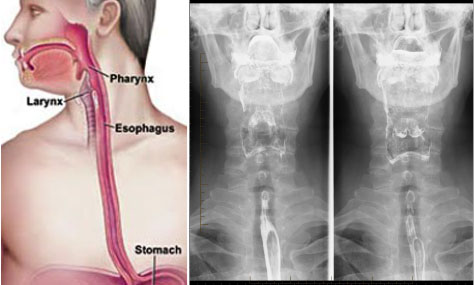

The left panel above shows the orientation of the pharynx and esophagus between the back of the mouth and stomach, respectively; and in the middle and right panels show the result of a normal barium swallow study in a static X-ray.